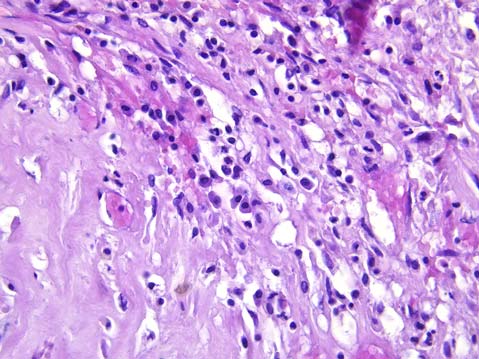

При патологоанатомическом вскрытии в левой плевральной полости около 1200,0 мл тёмно-красной крови, в виде сгустков и в жидком состоянии. Лёгкие тестоватой консистенции на всём протяжении, на разрезах лёгкие светло-красного цвета, с поверхностей разрезов при сдавливании стекает значительное количество пенистой жидкости. В правом лёгком в верхней доле находится очаг уплотнения диаметром до 5 см, белесоватого цвета. При гистологическом исследовании выявлена гумма, представленная очагом казеозного некроза с периферической диффузной и очаговой воспалительной инфильтрацией преимущественно из плазмоцитов, макрофагов, лимфоцитов, склерозом, признаками эндоартериитов (рис. 1, 2).

Рис. 1. Гумма в лёгком: очаг казеозного некроза, окружённый валом из воспалительных клеток. Окраска гематоксилином и эозином. Увеличение ×50

Рис. 2. Гумма в лёгком: вокруг очага казеозного некроза воспалительный инфильтрат из лимфоцитов, макрофагов, плазмоцитов, эндоартериит. Окраска гематоксилином и эозином. Увеличение ×200